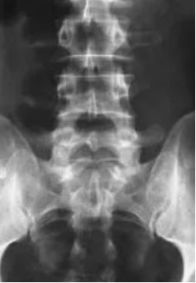

入院后,由薛杉副主任医师领衔的电生理团队,借助AI运动评估系统对患者进行了智能评估。结果显示,患者药物改善率高,其冻结步态属于药物反应性类型,适合通过精细的手术设计进行DBS治疗并从中获益。功能神经外科主任郭燕舞教授与学科带头人张世忠教授综合临床评估及多模态影像学检查结果,为患者量身定制了个体化DBS手术方案。手术中,张世忠教授与何骁征教授凭借精湛技艺,将电极精准植入预设靶点,并利用术中电生理监测技术实时验证触点位置,确保了手术的精确性。

可视化程控:使用Stimview XT系统可对患者磁共振(MRI)及CT影像进行定制化处理,自动划分核团轮廓、计算电极位置并直观呈现刺激场模型,使程控过程更加直观高效。

多靶点联合治疗:系统配备8触点电极,具有更长触点跨度,支持多靶点联合穿刺。针对冻结步态患者,可同时兼顾丘脑底核(STN)上方的未定带(ZI)及其下方的黑质网状部(SNr)进行协同刺激治疗。

这套脑起搏器通过融合患者影像数据模拟实时电刺激场与解剖结构的相对位置,医生可直观观测刺激场与神经核团的动态交互;结合独有的多重独立塑形刺激功能,为患者提供精细化、个体化的治疗方案。